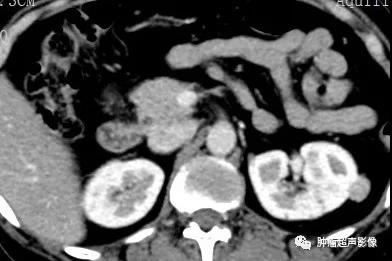

影像学检查对于TSC的诊断至关重要,且其表现具特征性,颅内病变以多发室管膜下结节伴钙化为特征,根据其部位分为4类:①室管膜下巨细胞星形细胞瘤(,由室管膜下结节生长而成,直径>1.3cm即称为室管膜下巨细胞星形细胞瘤,多发生于孟氏孔;②皮层及皮层下结节,好发部位依次为额叶、顶叶、枕叶、颞叶及小脑半球,表现为皮层增厚,脑回肥大,且病变多少与神经系统症状直接相关;③脑白质放射状移行线,代表着异位的神经元和神经胶质沿脑室向皮层移行路径;④脑白质病变。肾脏肿瘤内脂肪成分的出现即可确诊错构瘤,实性肿块、血供丰富为肾癌的特点,但有时缺乏脂肪成分的较小的血管平滑肌瘤亦不易与之鉴别。腹膜后或者肺内厚壁或者薄壁的囊性病变、肺内蜂窝状改变、腹膜后淋巴结增大、胸导管扩张及胸腹水等都是腹膜后及肺内淋巴管肌瘤病的表现。肝脏亦可发生异常,典型表现为肝实质内血管平滑肌脂肪瘤。表现为边界清晰的含有脂肪成分的低密度病变,此外肝脏肿大、肝脏肌脂瘤、脂肪瘤、错构瘤及纤维瘤都可发生。此外,胰腺萎缩、胰腺嗜铬细胞瘤、错构瘤及胰腺导管阻塞等胰腺病变均可发生。

超声检查发现双肾多发AML,尤其是肿瘤数目较多、瘤体较大、肾脏轮廓不清时要想到TSC的可能,并询问相关病史,并观察面部、建议颅脑CT检查等。肾囊肿在TSC中也较常见,是该病临床诊断的次要指征。肝AML在超声上与血管瘤表现类似,均表现为大小不等圆形或椭圆形偏强回声团块,肝AML含有脂肪成分,回声比血管瘤回声更强一些,结合TSC病史,肝脏多发偏强回声占位应首先考虑为AML。

女,61,因肾肿瘤入院治疗,超声及CT示两肾多发错构瘤,建议头颅检查。